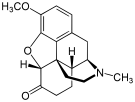

In the 19th century, two major scientific advances were made that had far-reaching effects. Around 1804, German pharmacist Friedrich Sertürner isolated morphine from opium. He described its crystallization, structure, and pharmacological properties in a well-received paper in 1817.[211][213][208][214] Morphine was the first alkaloid to be isolated from any medicinal plant, the beginning of modern scientific drug discovery.[211][215]

Several semi-synthetic opioids were developed in Germany in the 1910s. The first, oxymorphone, was synthesized from thebaine, an opioid alkaloid in opium poppies, in 1914.[228] Next, Martin Freund and Edmund Speyer developed oxycodone, also from thebaine, at the University of Frankfurt in 1916.[229] In 1920, hydrocodone was prepared by Carl Mannich and Helene Löwenheim, deriving it from codeine. In 1924, hydromorphone was synthesized by adding hydrogen to morphine. Etorphine was synthesized in 1960, from the oripavine in opium poppy straw. Buprenorphine was discovered in 1972.[228]

- Natural opiates: alkaloids contained in the resin of the opium poppy, primarily morphine, codeine, and thebaine, but not papaverine and noscapine which have a different mechanism of action

Opium alkaloids and derivatives

Opium alkaloids

Phenanthrenes naturally occurring in (opium):